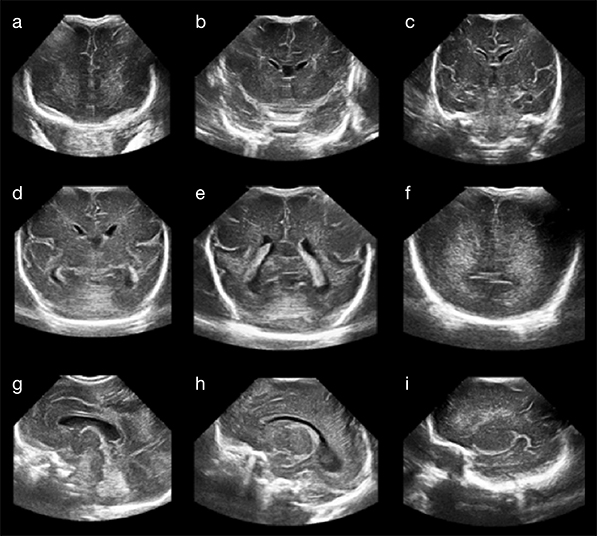

Naučnici sa Univerziteta za nauku i tehnologiju Huazhong, u Vuhanu, u Kini, uspešno su na životinjama testirali novi bežični mikromodul za praćenje zdravlje mozga, koji se u telo ubacuje pomoću injekcije, a posle nekoliko nedelja se potpuno istopi. Ova medicinska inovacija može da bude temelj razvoja minimalno invazivnih humanih implantata za praćenje stanja pacijenta posle traumatskih povreda mozga ili kod nekih neuroloških oboljenja kao što je npr. epilepsija.

Mikromodul je kocka mekog hidrogela stranice 2mm, sa finim unutrašnjim vazdušnim strukturama, formirana kao "metagel" senzor. Ta struktura omogućava mikromodulu da vrši refleksiju ultrazvučnih talasa, koji menjaju oblik kao odgovor na različite parametre u mozgu (kao što su pritisak ili temperatura), a spolja ih registruje sonda ultrazvučnog aparata. Metagel se praktično ponaša kao sićušno akustično ogledalo koje menja svoj odraz u skladu sa okruženjem.

Za ubacivalje senzora u mozak koristi se igla velikog prečnika, što samo po sebi može da izazove izvesnu nelagodu. Prilikom testova na zamorcima i svinjama, metagel senzori su merili pritisak, temperaturu, pH vrednosti i protok krvi, pokazujući rezultate koji nisu bili manje precizni od onih dobijenih tradicionalnim žičanim sondama. Metagel se kasnije, u roku od četiri do pet nedelja razgradio na bezopasne komponente: vodu i ugljendioksid.

Početni eksperimenti pokazali su minimalno oticanje tkiva i slab imunološki odgovor u mozgu zamorca nakon implantacije i resorpcije senzora, pa naučnici smatraju da će ovakva vrsta implantata u budućnosti sigurno pronaći primenu u aplikacijama za medicinsko praćenje i humanu dijagnostiku.